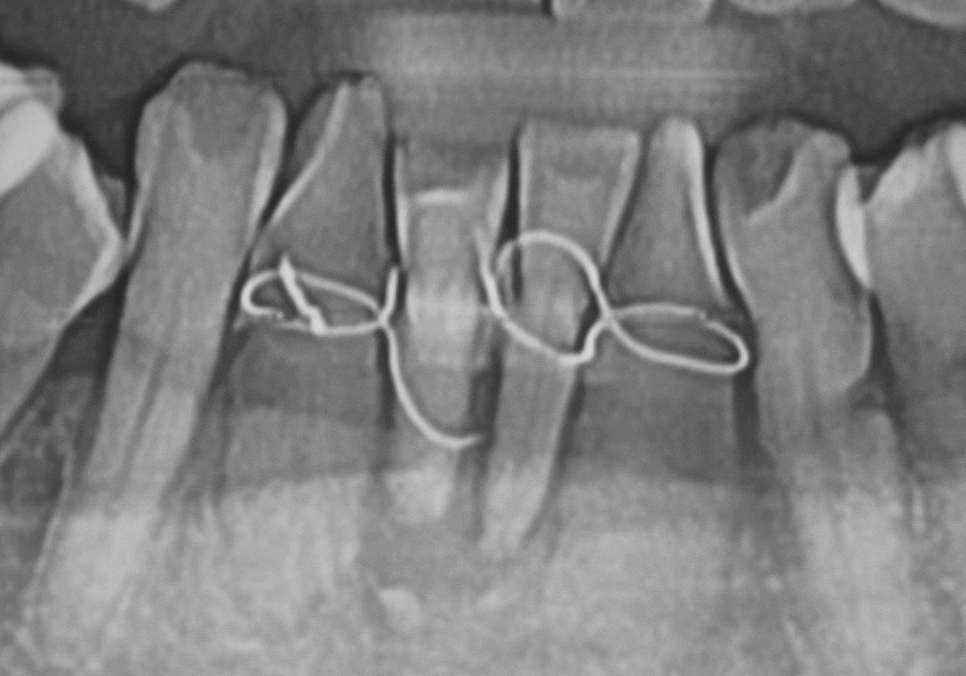

이 환자분은 과거에 아래

중앙 앞니(#31, 41)가 흔들리기 시작했을 때,

발치가 두려워 철사로

양옆 치아까지 넓게 묶어두셨다고 해요~

251022

당장 흔들림이 없으니

안심하고 오랜 시간을 보내셨지만,

정작 뿌리 끝에 박힌 염증 원인은

그대로 남아 있었죠.

결국 중앙 앞니에서 시작된 염증은

조용히 옆 치아(#32, 42)까지 퍼져나갔습니다.

내원 당시에는

이미 철사로도 감당할 수 없을 만큼

4개의 치아가 한꺼번에

심하게 흔들리고 있었고,

251028

주변 잇몸뼈가 광범위하게 녹아내려

결국, 앞니 4개를 모두 발치하고

임플란트를 진행했습니다.